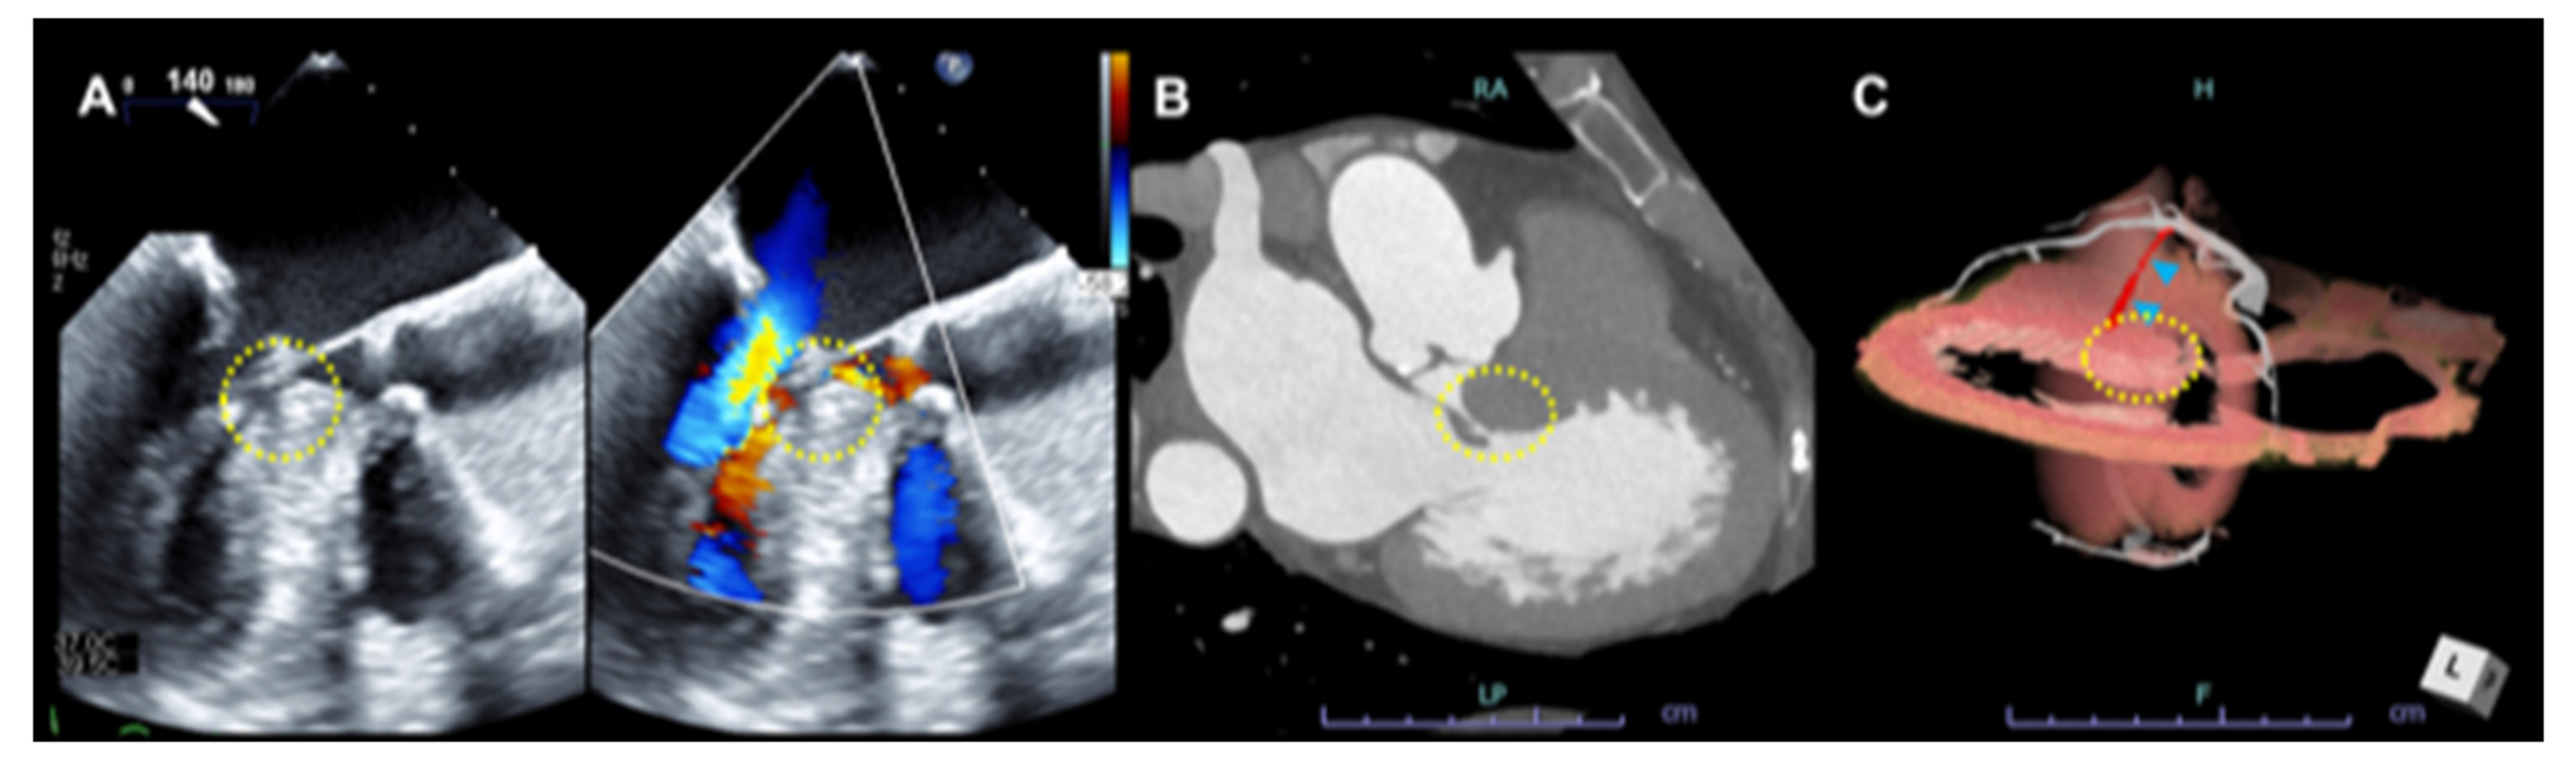

3.2. Systolic Anterior Motion (SAM) of the Mitral Valve and Anomaly in the Mitral Valve Apparatus

3.3. Mid-Ventricular Obstruction (MVO) and Left Ventricular Apical Aneurysm (LVAA)